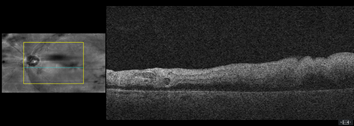

Dilated fundus examination revealed relatively normal fundus with cup-to-disc (C/D) ratio of 0.30 round OD (Figure 1A). The fundus photo of the left eye showed a pale posterior pole with swollen optic nerve head and macular cherry spot (Figure 1B). Ocular coherent tomography (OCT) macular cube scans showed a representative slice of normal retinal layers through the macula OD (Figure 2A), and a pigmented epithelial detachment and disrupted retinal layers extending temporally from the optic nerve head (ONH) OS (Figure 2B). Additionally, Figure 3 and Figure 4 showed the OCT optic disc cube 200x200 scan with swollen ONH OS, and OCT macular cube 512x128 scan with detached retinal layers OS, respectively.

Figure 2A a slice of OCT macular cube showing normal retinal layers OD.

Figure 2B a slice of OCT macular cube showing pigmented epithelial detachment, and disrupted retinal layers OS.